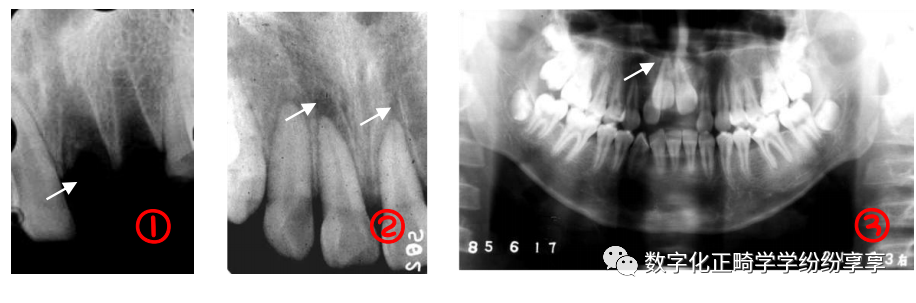

牙周病 Periodontitis:

牙槽骨水平型吸收

多数牙或全口牙槽骨从嵴顶呈水平方向向根尖高度减低,吸收程度较均匀,早期表现牙槽嵴顶骨硬板模糊,继而前牙区牙槽嵴顶由尖变平,后牙区牙槽嵴顶由梯形变凹陷,边缘模糊粗糙呈虫蚀样;随疾病进一步发展,牙槽嵴逐渐向根尖方向吸收。

牙槽骨垂直型吸收

表现为局部牙槽骨或牙槽间隔的一侧,沿牙体长轴方向向根端吸收,病变早期造成牙槽骨壁吸收,骨硬板消失,牙周间隙增宽;随病变加重,牙槽骨垂直吸收明显,呈楔形,若同一牙齿近远中均有垂直吸收,牙槽骨可见弧形吸收(吸收区域包绕两个及以上牙面)。

牙槽骨混合型吸收

牙槽骨在水平吸收的基础上,同时伴有个别牙或多数牙的牙槽骨垂直吸收。多见于牙周炎晚期。